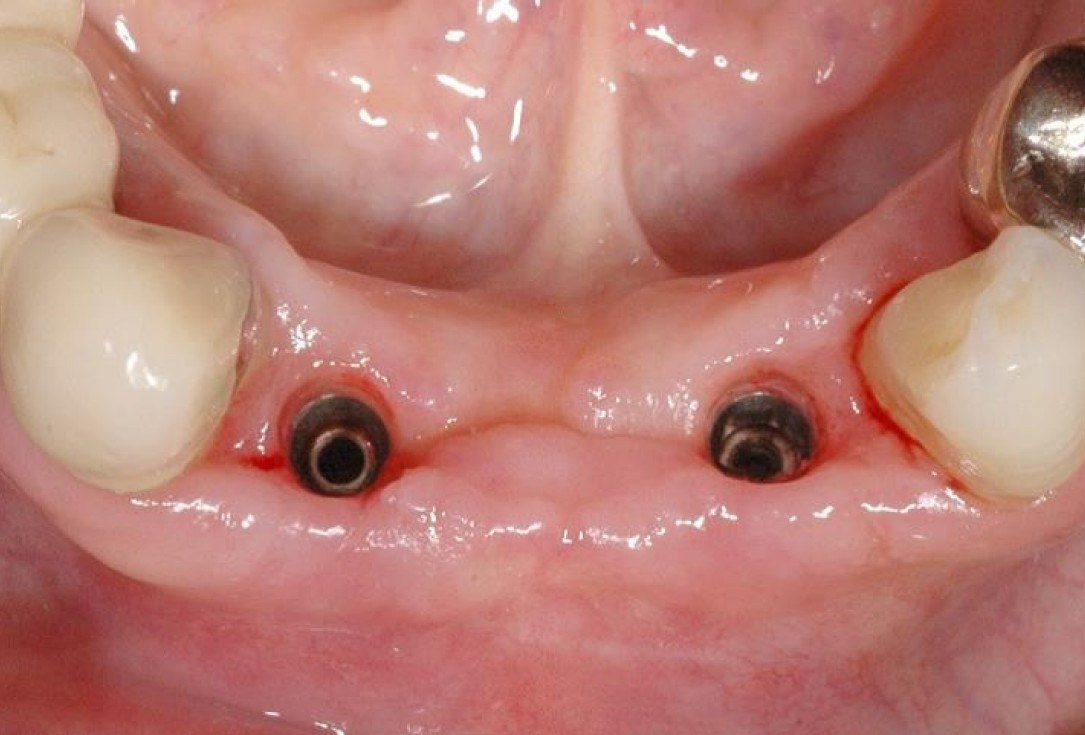

10/15 - Re-entry and removal of the non-resorbable membraneSoft tissue augmentation and GBR with mucoderm® and maxresorb® - Dr. S. Scherg